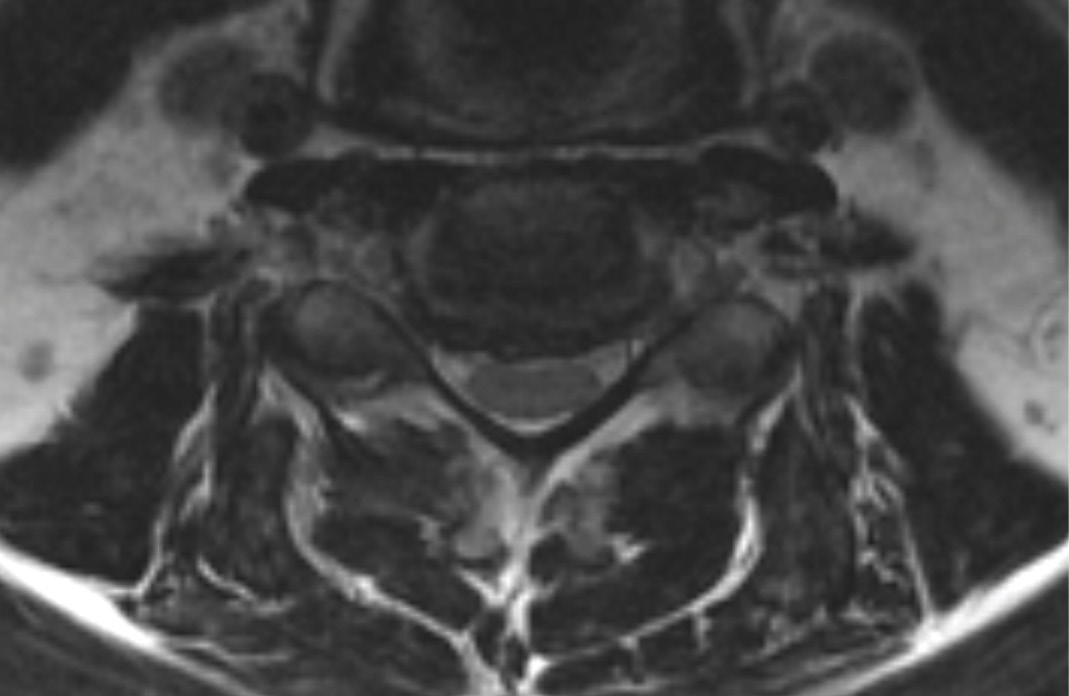

MRIs illustrated mild degenerative disc disease from C4-6 with disc herniations at both C4-5 and C5-6. The axial slice through C4-5 showed a right central disc herniation causing central and mainly right-sided foraminal stenosis. The axial slice through C5-6 showed a central disc herniation also causing central and mainly right-sided foraminal stenosis. The axial slice through C6-7 showed a left-sided disc herniation causing some left-sided foraminal stenosis, however, the patient did not demonstrate any left-sided symptoms.

During the procedure, prodisc C Vivo fit well within the C4-5 concave endplate. I expected to use a flat endplate prodisc C SK at C5-6, however I trialed the domed prodisc C Vivo and it actually looked good, so I unexpectedly used matching implants.

It was very helpful to have the flexibility to use either a flat or a domed implant at either level. Having the different size options available to truly match patient anatomy that the Match-the-Disc™ System provides enabled me to avoid having to alter the patient’s anatomy to fit the device.